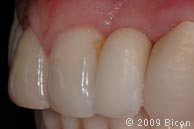

66. Вид интегрированной коронки (IAC).

67. Вид интегрированной коронки (IAC).

68. Вид спереди.